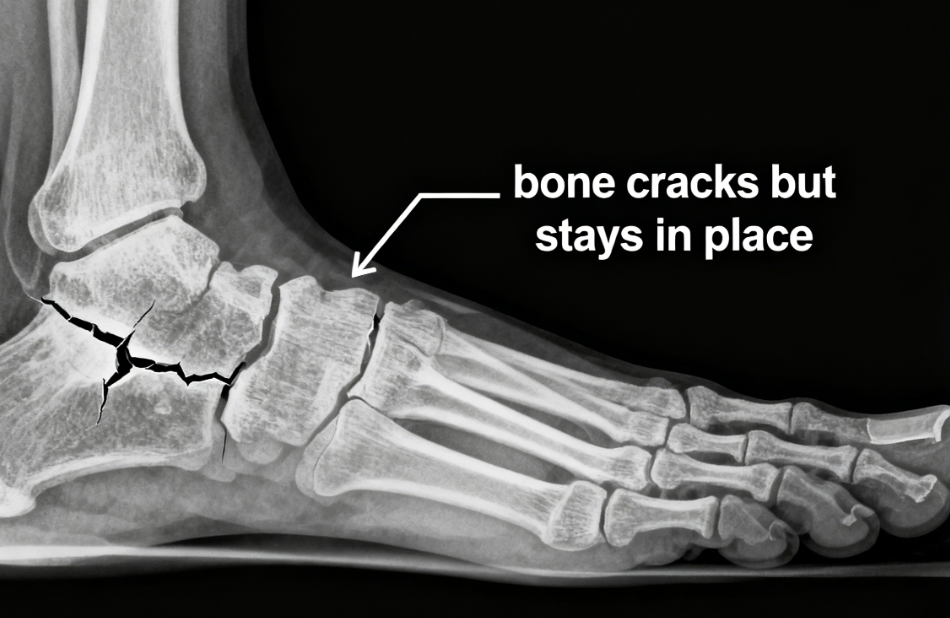

There are two main types:

Non-displaced fractures: The bone cracks but stays in place. It usually heals faster and is easier to manage.

Displaced fractures: The bone moves out of alignment. They often require medical intervention to realign properly.